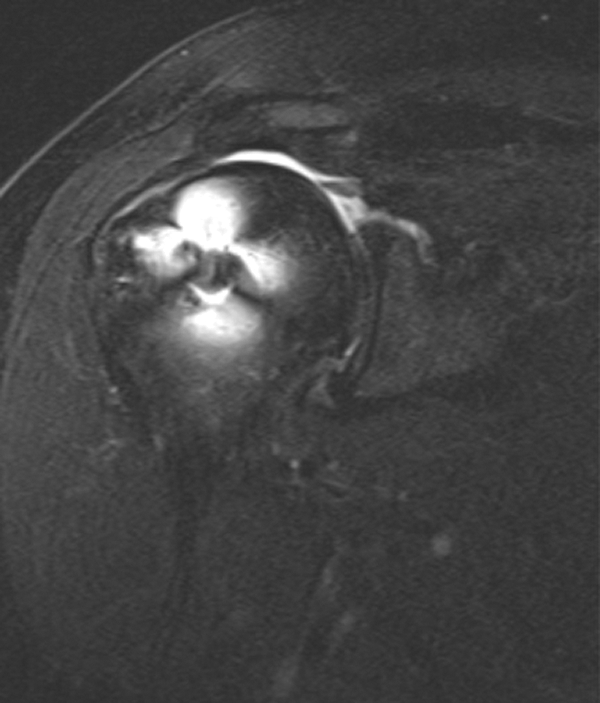

The patients were evaluated with MRI at a minimum of 12 months after surgery for tendon integrity. Postoperative MRI was performed with a 1.5-T Avanto scanner (Siemans AG). Postoperative MRI was evaluated for repair healing (Figures 6 and 7). Anatomic assessment of tendon healing was performed by a shoulder surgeon who did not perform the surgical procedures (P.N.C.), using the grading scale described by Sugaya et al. 14 Grades I through III were considered healed, while grades IV and V were considered unhealed. MRI was also evaluated for retear patterns as defined by Cho et al. 5 Cases were divided into type 1 retears if there was no remaining cuff tissue at the insertion site of the rotator cuff on the greater tuberosity or type 2 retears if a remnant of cuff tissue remained at the insertion site despite the retear.

This postoperative magnetic resonance coronal T2-weighted image demonstrates an intact repair.

This postoperative magnetic resonance coronal T2-weighted image demonstrates a repair that is not intact.